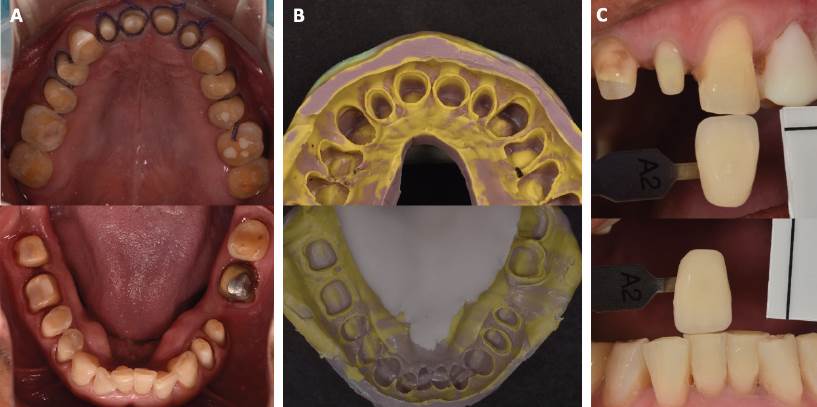

Se dejó un período de espera de seis semanas para lograr una estabilización en los tejidos gingivales. Se realizó una cucharilla individual de acrílico autopolimerizable (NicTone mdc® Dental, Zapopan, México) para la toma de impresión final. En esta etapa se colocaron hilos de retracción gingival de #0 y #000 (UltrapakTM, Ultradent Products Inc., Utah, Estados Unidos) humectados con líquido hemostático para lograr un perfil de emergencia en la impresión (Figura 2.A). Se procedió a tomar la impresión a 2 pasos utilizando silicón por adición (3MTM Imprint IITM, 3M Espe Deutschland GmbH, Alemania) (Figura 2.B). Se realizó toma de color con colorímetro (ips e.max® Ceram, Ivoclar Vivadent AG, Liechtenstein) con tono A2 (Figura 2.C).

Figura 2 Impresión y toma de color. A. Colocación de hilos retractores para toma de impresión. B. Impresiones definitivas de polivinilsiloxano. C. Registro de color.